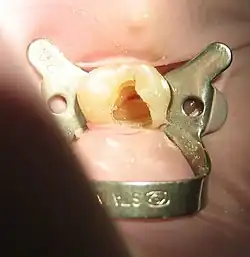

W zależności od rozpoznania lekarz wybiera odpowiednią metodę leczenia kanałowego. Jednak w dużym uproszczeniu, dla ogólnego zrozumienia aspektu leczenia kanałowego, przebieg leczenia wygląda następująco:

- Otwarcie komory zęba i usunięcie martwej lub żywej miazgi (żywą usuwa się w znieczuleniu miejscowym).

- Opracowanie kanału lub kanałów korzeniowych przy użyciu narzędzi kanałowych z obfitym płukaniem kanałów. W trakcie opracowywania kanałów korzeniowych następuje całkowite usunięcie miazgi kanałowej z kanału korzeniowego oraz toksyn bakteryjnych z kanalików zębinowych, dzięki czemu poszerzony kanał staje się odpowiednio przygotowany do wypełnienia. Do przepłukiwania kanałów stosowany jest między innymi podchloryn sodu.

- Osuszenie kanałów.

- Wypełnienie kanałów materiałami biozgodnymi. Czynność ta ma na celu szczelne zamknięcie światła kanału na całej długości do otworu fizjologicznego, aby uniemożliwić przenikanie bakterii z jamy zęba do tkanek okołowierzchołkowych. Wypełnianie kanałów korzeniowych wymaga zastosowania różnych materiałów i technik. Materiały wypełniające możemy podzielić na stosowane czasowo i stosowane na stałe do ostatecznego wypełnienia. Najpopularniejszym materiałem do wypełniania kanałów korzeniowych na stałe jest gutaperka, która stosowana od blisko 100 lat, mimo wielu nowych materiałów, jest najlepszym wypełniaczem kanałów, dającym doskonałe efekty lecznicze.

- Wypełnienie zęba. Najczęściej prawidłowo przeleczony ząb wypełnia się materiałami kosmetycznymi, do których należą materiały kompozytowe, kompomerowe i nowe materiały ormocerowe.